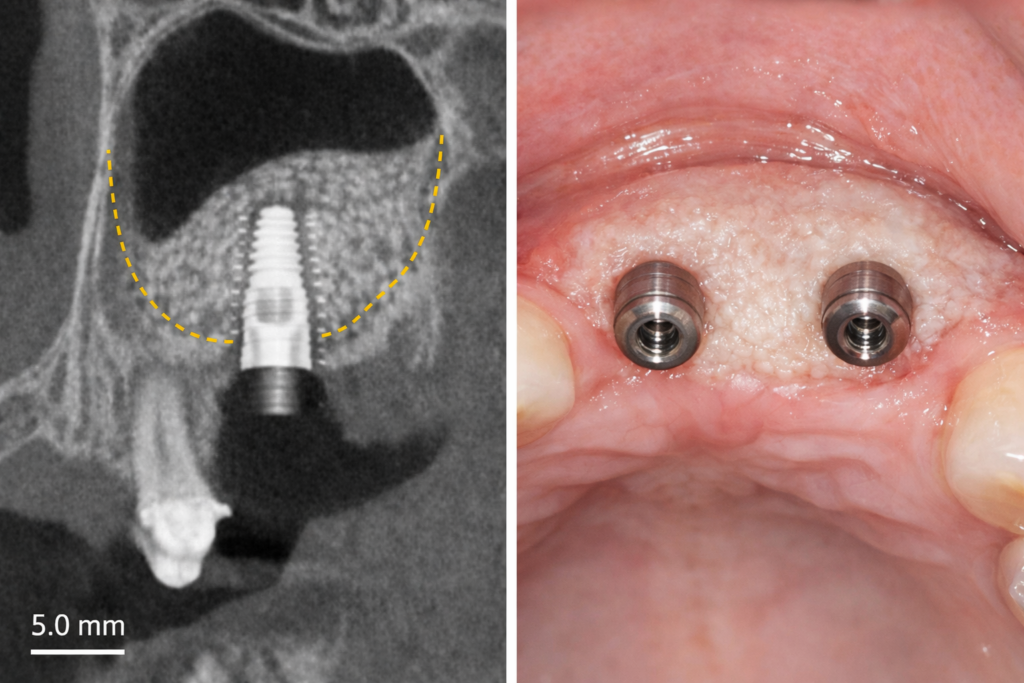

【写真③:治癒後・骨再生後のCTまたはインプラント埋入後】

※骨がしっかり再生されている様子